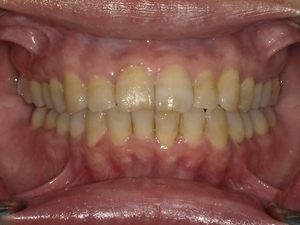

○ご相談内容:下の歯のがたつき○矯正の種類:マウスピース型矯正「クリアコレクト」○治療期間:10週間○治療費用:66万円(税込)